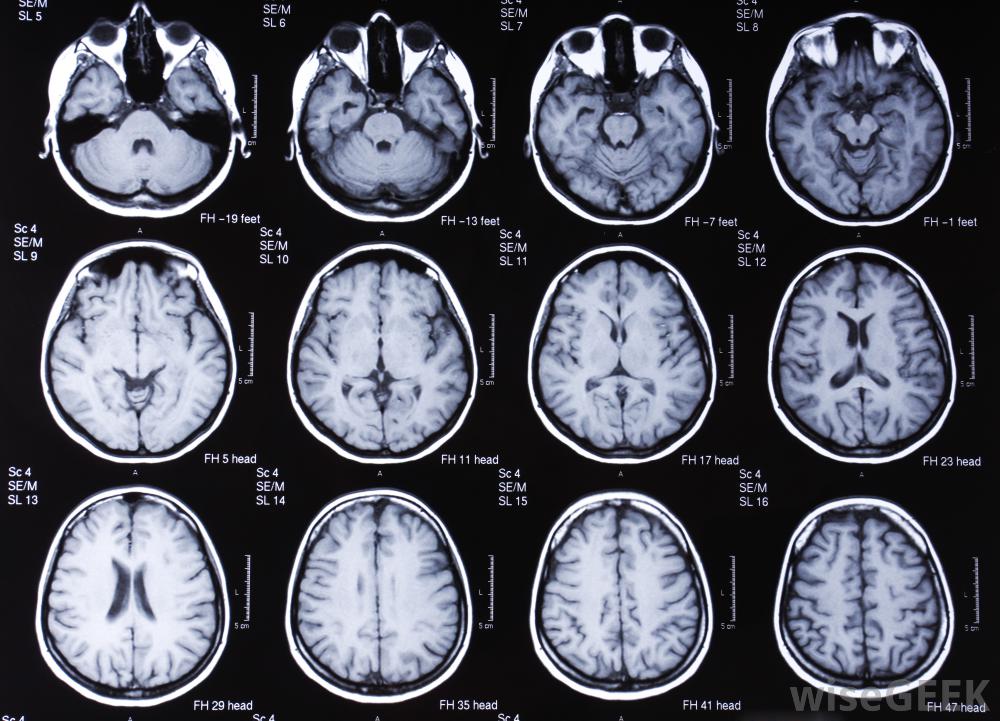

头晕和呕吐的一些最常见的原因包括内耳感染、怀孕、低血糖和脑震荡。此外,肾病、高血压或低血压以及严重贫血也会导致这些症状。虽然大多数头晕和呕吐的病例是短暂的,但持续和严重的症状需要进行医学评估。这些疾病的诊断测试包括妊娠评估、全血细胞计数、血液化学特征和耳朵检查。此外,如果怀疑脑震荡或其他头部损伤,可以进行核磁共振或CT扫描

如果怀疑头部受伤是头晕和呕吐的原因,则建议进行脑部核磁共振检查。